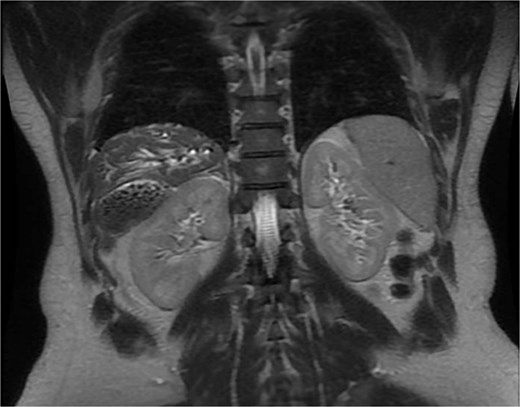

A 35-year-old male, medically free, presented to the emergency department with a 3-day history of epigastric abdominal pain. The pain was gradual in onset, colicky, non-radiating, and aggravated by fatty meals. It was partially relieved by analgesia. He reported nausea with two episodes of vomiting and dark urine, but denied fever, rigors, or bowel habit changes. His past surgical history included laparoscopic sleeve gastrectomy performed 7 years earlier, with subsequent weight loss of 40 kg, and anal fistulotomy 1 year prior. On examination, the patient was alert, oriented, and afebrile. Conjunctival icterus was noted. Abdominal examination revealed right upper quadrant and epigastric tenderness with a positive Murphy’s sign. Laboratory investigations showed: hemoglobin 14.8 g/dl, WBC 5 × 109/l, Alanine Aminotransferase (ALT) 341 U/l, Aspartate Aminotransferase (AST) 96 U/l, Alkaline Phosphatase (ALP) 250 U/l, Gamma-Glutamyl Transferase (GGT) 21 U/l, total bilirubin 121.9 μmol/l, and direct bilirubin 86.7 μmol/l. Ultrasound was done revealed multiple gallstones with gallbladder wall thickening, a dilated common bile duct (8 mm). Magnetic resonance cholangiopancreatography (MRCP) done and demonstrated an abnormally located subhepatic gallbladder, innumerable gallstones and sludge in a distended gallbladder with an 8 mm stone impacted at the gallbladder neck, moderate CBD dilation (1.1 cm), and a 6 × 4 mm distal CBD stone. (Fig. 1) Intrahepatic biliary radicles were dilated with a mildly irregular contour concerning for cholangitis. (Fig. 2).

MRCP showing the gallbladder is markedly distended and contains multiple gallstones and sludge, with an impacted stone at the gallbladder neck. Associated dilatation of the common bile duct and intrahepatic biliary radicles is noted, consistent with obstructive biliary pathology.